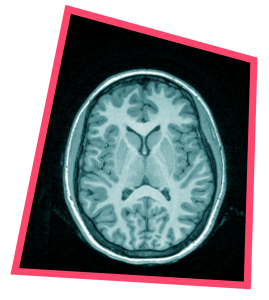

“Het brein vind ik echt magisch. Het is een beetje als het heelal. Aan de ene kant heel alledaags, iedereen heeft het, en aan de andere kant heel complex, en ondoorgrondelijk. Hoe alle neuronen samenwerken, daar begrijpen we eigenlijk nog steeds weinig van.”

“Tijdens mijn studie in Pittsburgh leerde ik hoe je met fMRI hersenactiviteit in kaart kunt brengen terwijl iemand een taak uitvoert. Terug in Nederland zette ik een lab op om te onderzoeken hoe risicogedrag van jongeren samenhangt met emoties. Bij volwassenen was al bekend dat emotiekernen daarin een rol spelen, en ik wilde nagaan hoe die rationele en emotionele hersendelen samenwerken in het puberbrein. In 2005 startte ik mijn eerste experimenten. Via lezingen, waarin ik vertelde over mijn boek Het Puberbrein, meldden zich zó veel enthousiaste ouders en jongeren aan dat ik meer deelnemers had dan ik mee kon laten doen.

“Via de fMRI keken we wat er in de hersenen gebeurt terwijl het risico in het gokspel opliep en de persoon het goed of fout had. We bestudeerden verschillende emotiekernen, met een hoofdrol voor het ventrale striatum. Dat is een emotiekern die reageert op prikkels van risicogedrag. Die hersendelen worden vaak gezien als dé reden dat jongeren gaan vapen, alcohol drinken of de regels overtreden.”

“We ontdekten dat precies dezelfde hersensystemen actief werden wanneer jongeren het gokspel voor zichzelf, voor vrienden of voor hun ouders deden. Het gebied waarvan we altijd dachten dat het ‘slecht’ pubergedrag verklaarde, bleek dus óók belangrijk voor positief sociaal gedrag. Ik dacht echt: ‘Wauw, dit zet de hele adolescentiepsychologie op z’n kop.’